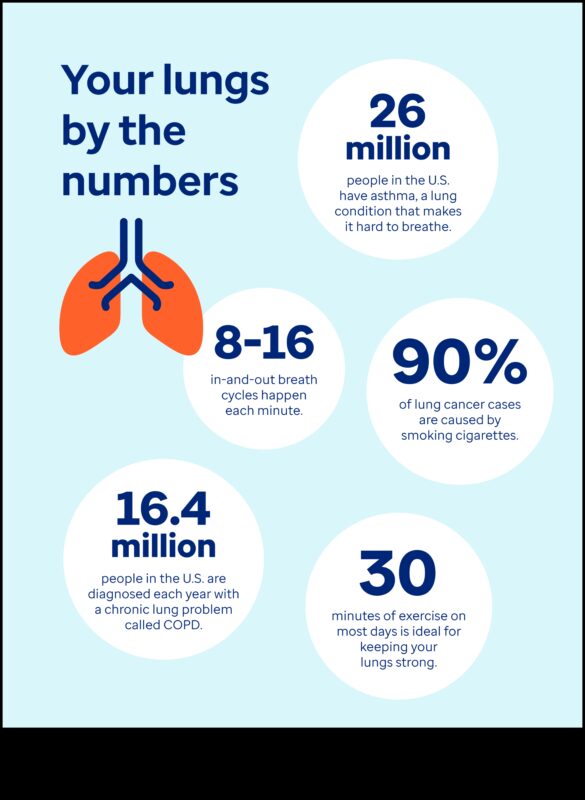

Elpošanas treniņu rutīnas varētu arī atbalstīt spēcināt plaušu darbību un minimizēt astmas simptomus. Viens no svarīgākajiem visizplatītākajiem astmas elpošanas vingrinājumiem ir:

Elpošanas treniņu rutīnas ir seifs un labs veids, padomi, kā spēcināt plaušu darbību un minimizēt astmas simptomus. Ja Jums ir bronhiālā astma, konsultējieties izmantojot savu ārstu attiecībā uz elpošanas vingrinājumu pievienošanu ārstēšanas plānam.

Ir dažādība elpošanas treniņu rutīnas, kas varbūt atbalstīt vecākiem izmantojot astmu kontrolēt simptomus. Tie treniņu rutīnas varētu arī atbalstīt spēcināt plaušu darbību, minimizēt iekaisumu un minimizēt elpas trūkumu.

Astmas slimniekiem pastāvīgi notiek elpas zaudējums, sēkšana un klepus. Tie indikatori parasti ir novājinoši, apgrūtinot standarta darbību veikšanu. No otras puses ir dažādība treniņu rutīnas, kas astmas slimniekiem varētu arī atbalstīt pacelt elpot. Tie treniņu rutīnas varētu arī spēcināt plaušas un spēcināt elpošanas talanti, atvieglojot elpošanu astmas lēkmes gaitā.

Elpošanas vingrinājumiem ir liels skaits ieguvumu, tostarp:

Elpošanas treniņu rutīnas varētu arī atbalstīt spēcināt plaušu kapacitāti, spēcināt elpošanas muskuļus un spēcināt vispārējo elpceļu veselību. Šie varētu arī atbalstīt jums kontrolēt astmas, HOPS un citu elpošanas traucējumu simptomus.